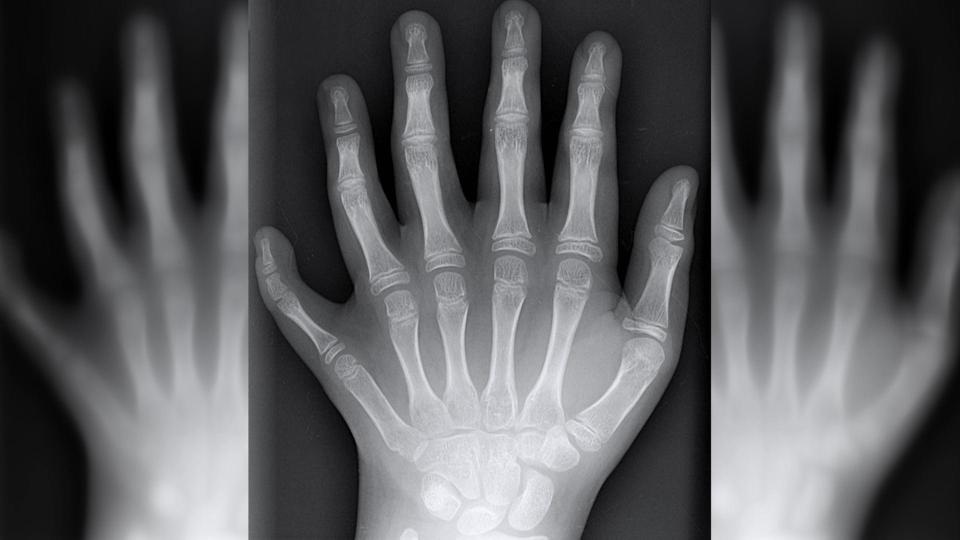

Người đàn ông cho biết tình trạng của gia đình mình là do chứng polydactyly (dị tật thừa ngón) và chỉ xảy đến với tỷ lệ 1/1.000 đứa trẻ. Dù vậy, khả năng xảy ra tình trạng này trong dòng họ De Silva là khá cao. Ví dụ như Alessandro, do kết hôn với một người phụ nữ bình thường nên con trai Vinicius của họ có 50% cơ hội sở hữu gien 6 ngón trên một bàn tay.

“Chúng tôi phát hiện Vinicius là một cậu bé vào tuần thai thứ 13 và từ lúc đó, chúng tôi đã hy vọng rằng con sẽ có 6 ngón trên một bàn. Quả thật khi ra đời, thằng bé đã có được điều đó, các ngón tay của nó cũng hoạt động bình thường”, bà mẹ Katia chia sẻ.

Con trai đầu lòng của Alessandro là Guillherme cũng có 12 ngón tay, 12 ngón chân ngay từ lúc mới sinh. Cậu bé 7 tuổi rất tự hào về đặc điểm này và còn khẳng định có nhiều ngón tay giúp mình cầm nắm được nhiều thứ hơn. Anh họ của Guillherme là Maria và Joao Assis còn cho rằng 6 ngón tay trên một bàn giúp ích cho việc học piano và làm thủ môn bóng đá rất nhiều.